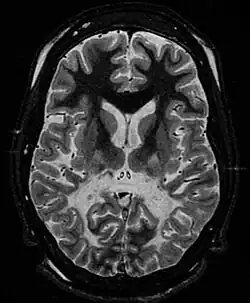

| T2 weighted axial scan of a human brain at the level of the caudate heads demonstrates marked loss of posterior white matter, with reduced volume and increased signal intensity. The anterior white matter is spared. Features are consistent with X-linked adrenoleukodystrophy. | |

The degeneration of white matter, which reflects the degeneration of myelin, can be seen in a basic MRI and used to diagnose leukodystrophies of all types. T-1 and T-2 weighted fluid-attenuated inversion recovery (FLAIR) images are the most often used approach.[25] Electrophysiological and other kinds of laboratory testing can also be done. In particular, nerve conduction velocity is looked at to distinguish between leukodystrophy and other demyelinating diseases, as well as to distinguish between individual leukodystrophies. For example, individuals with X-ALD have normal conduction velocities, while those with Krabbe disease or metachromatic leukodystrophy have abnormalities in their conduction velocities.[25] Multigene sequencing panels for undifferentiated leukodystrophy are offered for rapid molecular diagnosis after genetic counselling.